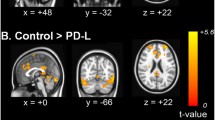

Then, the FC alteration of R.BF123-R.PO was further analyzed. As a result, no statistical difference between two PD groups was observed in OFF status (p = 0.523); however, in ON status, a decreased FC was observed for DA-responsive tremor compared with DA-resistant tremor group (p = 0.040). Compared with OFF status, the FC in ON status was unchanged for DA-resistant tremor patients (p = 0.475), while for DA-responsive tremor subjects was decreased (p = 0.003) (Table 2, Fig. 3).

1) The FC alteration of R.BF123-R.PO was further analyzed for two PD groups regarding NC as reference. As a result, no significant difference in OFF status was observed. In ON status, comparing with NC, the FC of R.BF123-R.PO was decreased for DA-responsive tremor patients (p = 0.038, uncorrected), while which was unchanged for DA-resistant tremor patients (p = 0.425) (Fig. 3, Table 3).